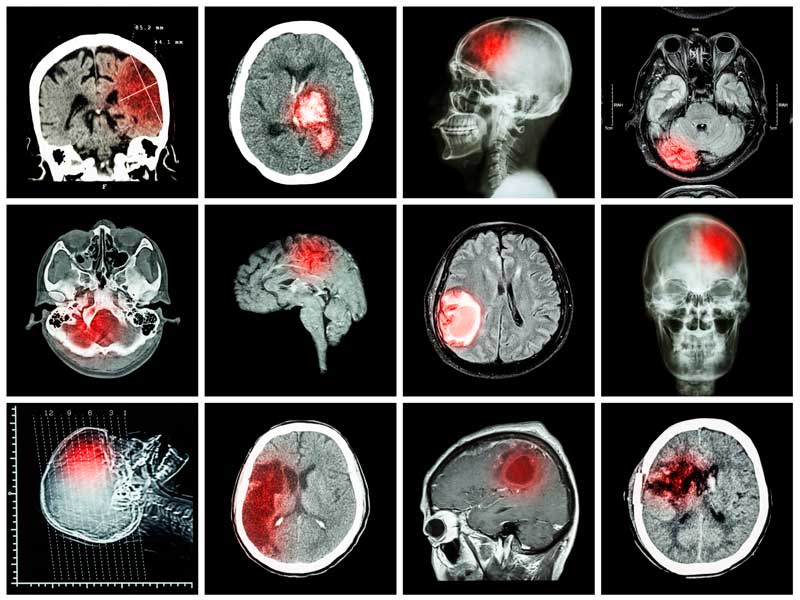

- Компьютерная томография и МРТ показывают наличие новообразований, признаки инсульта, воспалительных заболеваний, рассеянного склероза, болезни Альцгеймера, Паркинсона, сосудистых нарушений.